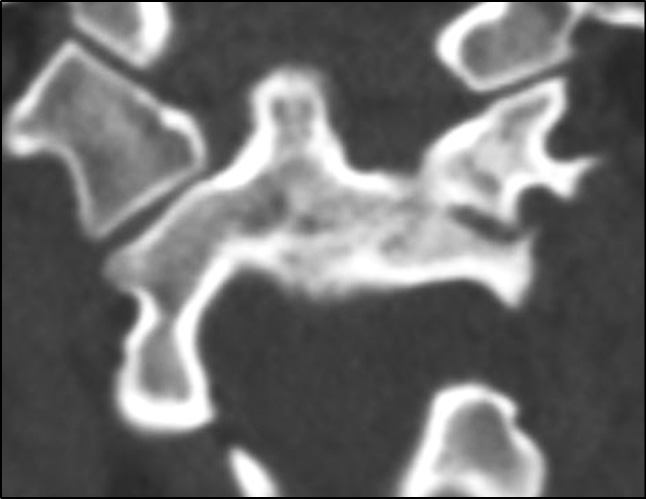

CT revealed gross violations of craniovertebral relationships: the Cruveilhier joint gap (atlantodental interval [ADI]) was 1.06 cm, and the space available for the spinal cord at the C1 level (SAC C1) was 5.17 mm. These changes indicate gross stenosis of the spinal canal. A bone block developed in the left lateral atlantoaxial joint (Fig. 3)

Fig. 3. Bone fusion in the region of the left lateral atlantoaxial joint.

Given the gross atlantoaxial dislocation with spinal canal stenosis, spinal cord compression, and bone block formation in the left lateral atlantoaxial joint, correction of C1 subluxation under intraoperative halo-traction with the release of the left lateral atlantoaxial joint was decided. To improve the quality of preoperative planning and reduce the risks of a. vertebralis injury during the release of the lateral atlantoaxial joint, the patient underwent CT and myelo- and angiography of the cervical spine (Fig. 4). A customized 3D model of the craniovertebral region was made, showing the vertebral arteries and spinal cord based on CT myelography and CT angiography (Fig. 5).